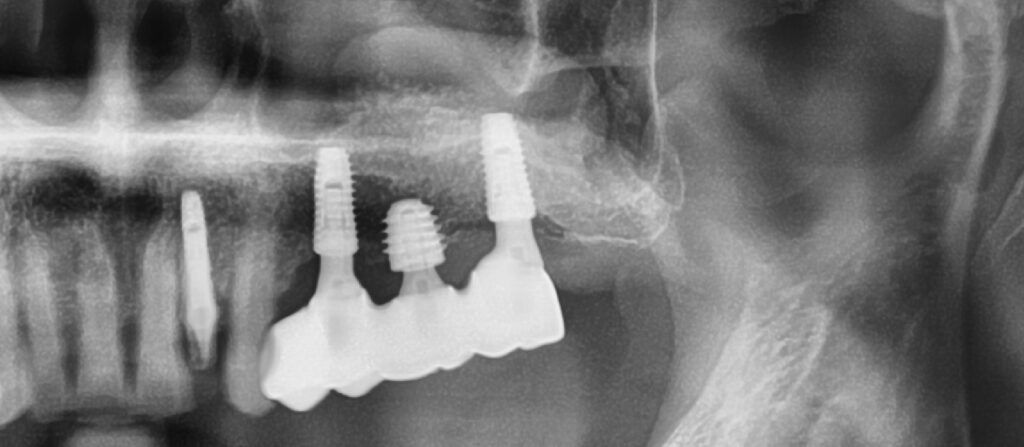

그렇다면 이런 케이스의 변화는 어떻게 되었을까요

상악동 거상술+점액종 제거술을 본원에서 시행한 후 완료된 사진입니다

가운데 임플란트에 비하여 훨씬 길고 안정되게 식립한 것을 볼 수 있습니다

한가지로 정리하면요

이정도의 상악동 거상술이면 안정되고 오랜 수명을 생각할 수 있을 듯 합니다